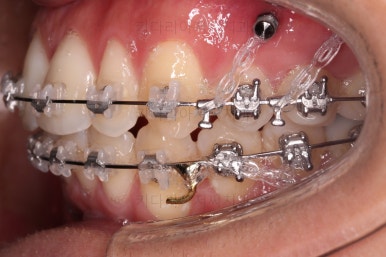

미니스크류도 일반적인 위치가 아니라 전반적인 치열의 높낮이를 조절하기에 용이한 위치에 갯수도 매우 많이 식립하게 됩니다.

한참을 셋팅한 방향으로 치열을 당겨줍니다.

중간평가를 자주 하게 됩니다.

입을 다물었을 때 턱끝이 점점 자연스러워지는 느낌이네요. 윗입술 부위가 둥글게 돌출되어 보이던 느낌도 점점 좋아지고 있고요.

아직은 환자분이 개선을 더 원하기 때문에 현재의 방식으로 더 진행하기로 했습니다.